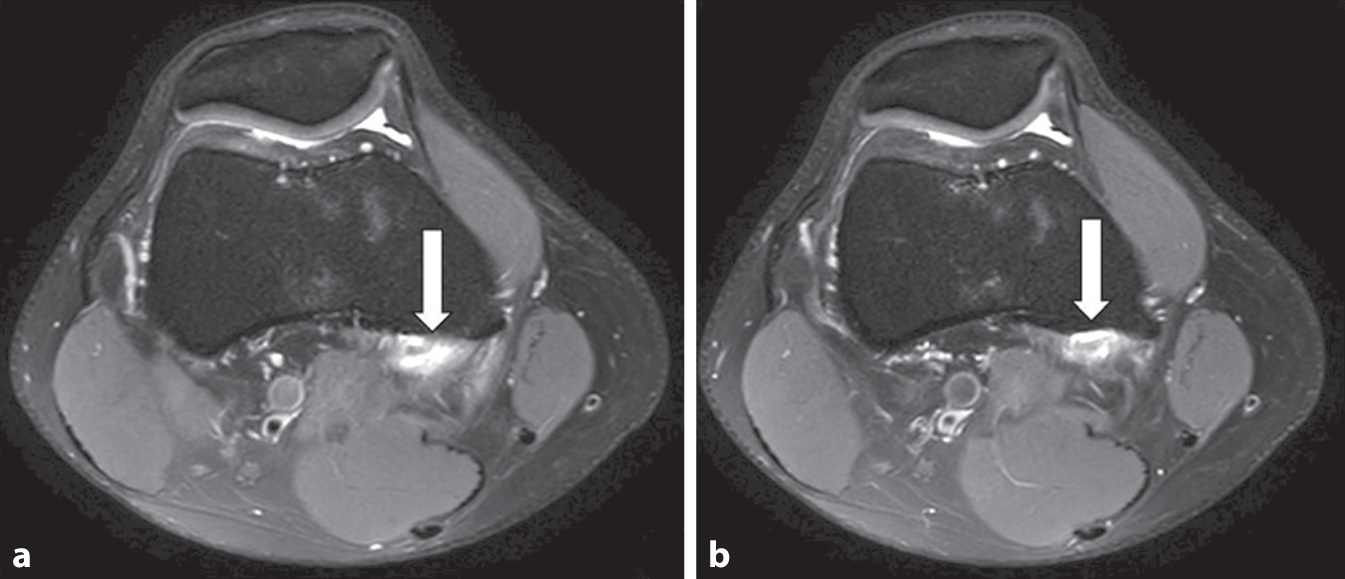

Fig. 1

ab Axial images indicating the partial tendon rupture of the medical gastrocnemius head

The MRI findings confirm the presence of a partial tear at the insertion site of the medial gastrocnemius head, with associated bone marrow edema, while ruling out any significant abnormalities in the medial and lateral compartments, menisci, collateral ligaments, and biceps tendon.